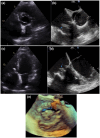

Infective endocarditis (IE) is an increasingly recognized condition with high morbidity. Patients with atypical symptoms, culture-negative infections, and prosthetic cardiac devices and implants represent challenging populations to evaluate and manage. Recent major society guidelines have recommended the appropriate incorporation of multimodality imaging in the evaluation of these more complex IE cases. This article draws on the available literature regarding the different cardiac imaging modalities and discusses the role of multimodality imaging in IE.